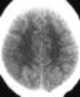

Global cerebral ischemia

Brain ischemia is a condition in which there is insufficient blood flow to the brain to meet metabolic demand. This leads to poor oxygen supply or cerebral hypoxia and thus leads to the death of brain tissue or cerebral infarction / ischemic stroke. [Source: Wikipedia ]